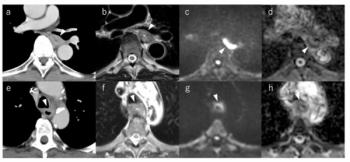

In the study of 8,992 patients (including 572 patients with type 2 diabetes), the study authors utilized a deep learning system to segment the pancreas and provide measurements of pancreas fractal dimension, CT attenuation and fat content. Other assessed biomarkers included visceral fat, liver CT attenuation and atherosclerotic plaque, according to the study, which was published in

The researchers found that patients with diabetes had lower average pancreatic CT attenuation (mean of 18.74 HU vs. 29.99 HU) and greater visceral fat volume (mean of 235 mL vs. 130.9 mL) in comparison to those without diabetes. The study authors also noted that greater duration of diabetes also corresponded with a progressive decrease in pancreatic attenuation.

Pointing to the findings from the multivariable analysis, the study authors said the CT-derived factors had “considerable predictive power.” Five of the six optimal factors for predicting type 2 diabetes were CT measures of total and eroded volumes of intrapancreatic fat percentage, pancreas fractal dimension, average liver attenuation and plaque severity between the L1 and L4 vertebra levels.